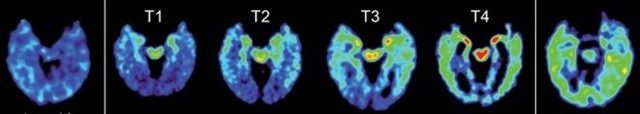

For the study, they were injected with a substance that binds to deposits of an abnormal protein found in CTE and makes them visible on a PET scan. The resulting PET images differed from results with 28 healthy people and 24 people with Alzheimer’s disease, a condition that can resemble CTE in its symptoms.